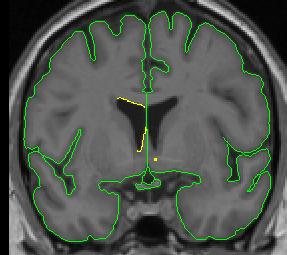

When the caudate is present two histograms are needed to define the two different borders of the ventricle.

1. Draw the first circle and create a contour for the CSF/white matter border (see above). This contour line is not a good measure of the border between the caudate and the CSF, so a separate line will need to be created for that section.

2. Clip the two ends of the CSF/white matter line where the caudate lies. For the purposes of the lateral ventricles, we consider the thalamus white matter, meaning its border with the lateral ventricle is the same contour line as the CSF/white matter line.

3. Use the "v" function to "save" the line.

4. Create a line for the CSF/caudate border. Your histogram circle should be half-way in the caudate and half-way in the CSF.

lateral ventricle 2 lateral ventricle 3

lateral ventricle 4 lateral ventricle 5

1. You may need to manually connect your "saved" contour to the new contour. By convention, in cases in which the caudate is present, include the most inferior extent of the CSF/white matter border as the lateral ventricle border, even if that necessitates drawing a short line from it to the CSF/gray matter border.